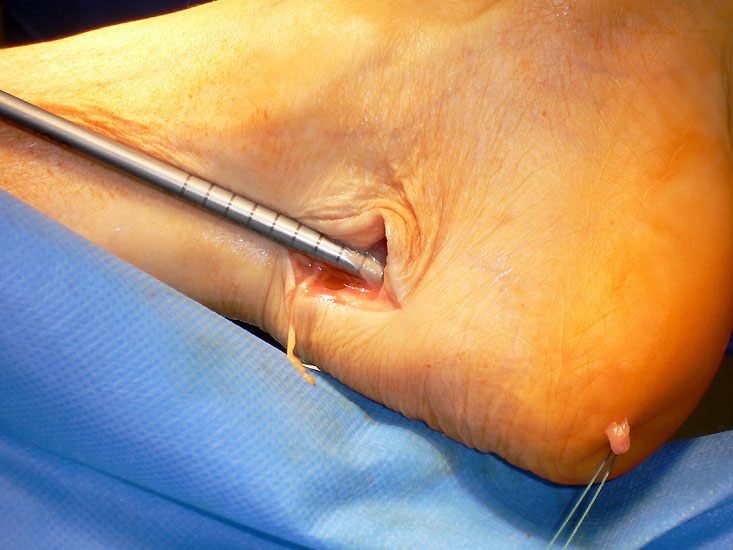

Abbildung 1

• Schwere, langstreckige degenerative Veränderungen der Achillessehne mit Ruptur (Abb. 1).